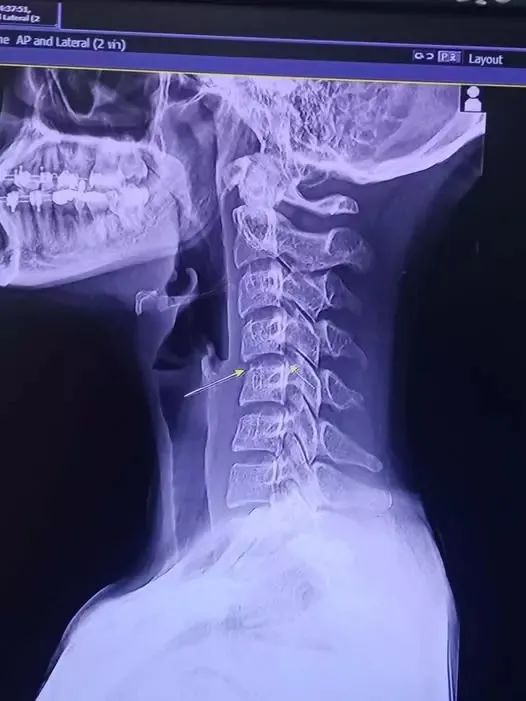

据《曼谷邮报》报道,受害者死于血液感染脑肿胀。前后几次按摩,皆采用了“扭颈”招式,这可能是涉事的关键。泰国Rangsit大学东方医学教授Thiravat表示,在颈部伸展运动过程中,剧烈扭动颈部可能损害颈动脉和椎动脉,尤其后者受损可能导致中风。警方随即对该按摩机构展开调查。然而,这家按摩店和所有技师均持有正规执照。

泰式按摩中的踩背行走叫做Ashi-Thai,据说是通过有节奏的按压,改变慢性软组织损伤的结构,并提供持续的催眠和深度放松。然而它与扭脖、折腰等特色招式同等重要,成为了造成损伤的关键节点。Chayada的死亡可见按摩脖子的脆弱性。